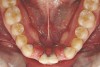

Figure 4a  Corticotomy SFOT. A 42-year-old male presented with a history of extraction orthodontic therapy (A). Incisors were too upright and had severe incisal wear. He was concerned about esthetics of the worn teeth and his insufficient lip support.

Figure 4a

Figure 4b  Progress photo and panorex 9 months after corticotomies were performed on Nos. 6 through 11 (B and C). Previous extraction sites were reopened orthodontically to improve function and fill lip support. Incisal edges were restored provisionally with composite resin. Note that despite the creation of adequate spaces to replace missing teeth, there is inadequate room for placement of dental implants because of severe tipping of all the anterior teeth. Osteotomy SFOT may have been a better choice because it would have allowed needed alveoloskeletal correction (without excessive tipping) instead of the primarily dentoalveolar correction common in corticotomy SFOT. Restorative dentist: Brad Jones, DDS.

Figure 4b

Figure 4c  Progress photo and panorex 9 months after corticotomies were performed on Nos. 6 through 11 (B and C). Previous extraction sites were reopened orthodontically to improve function and fill lip support. Incisal edges were restored provisionally with composite resin. Note that despite the creation of adequate spaces to replace missing teeth, there is inadequate room for placement of dental implants because of severe tipping of all the anterior teeth. Osteotomy SFOT may have been a better choice because it would have allowed needed alveoloskeletal correction (without excessive tipping) instead of the primarily dentoalveolar correction common in corticotomy SFOT. Restorative dentist: Brad Jones, DDS.

Figure 4c